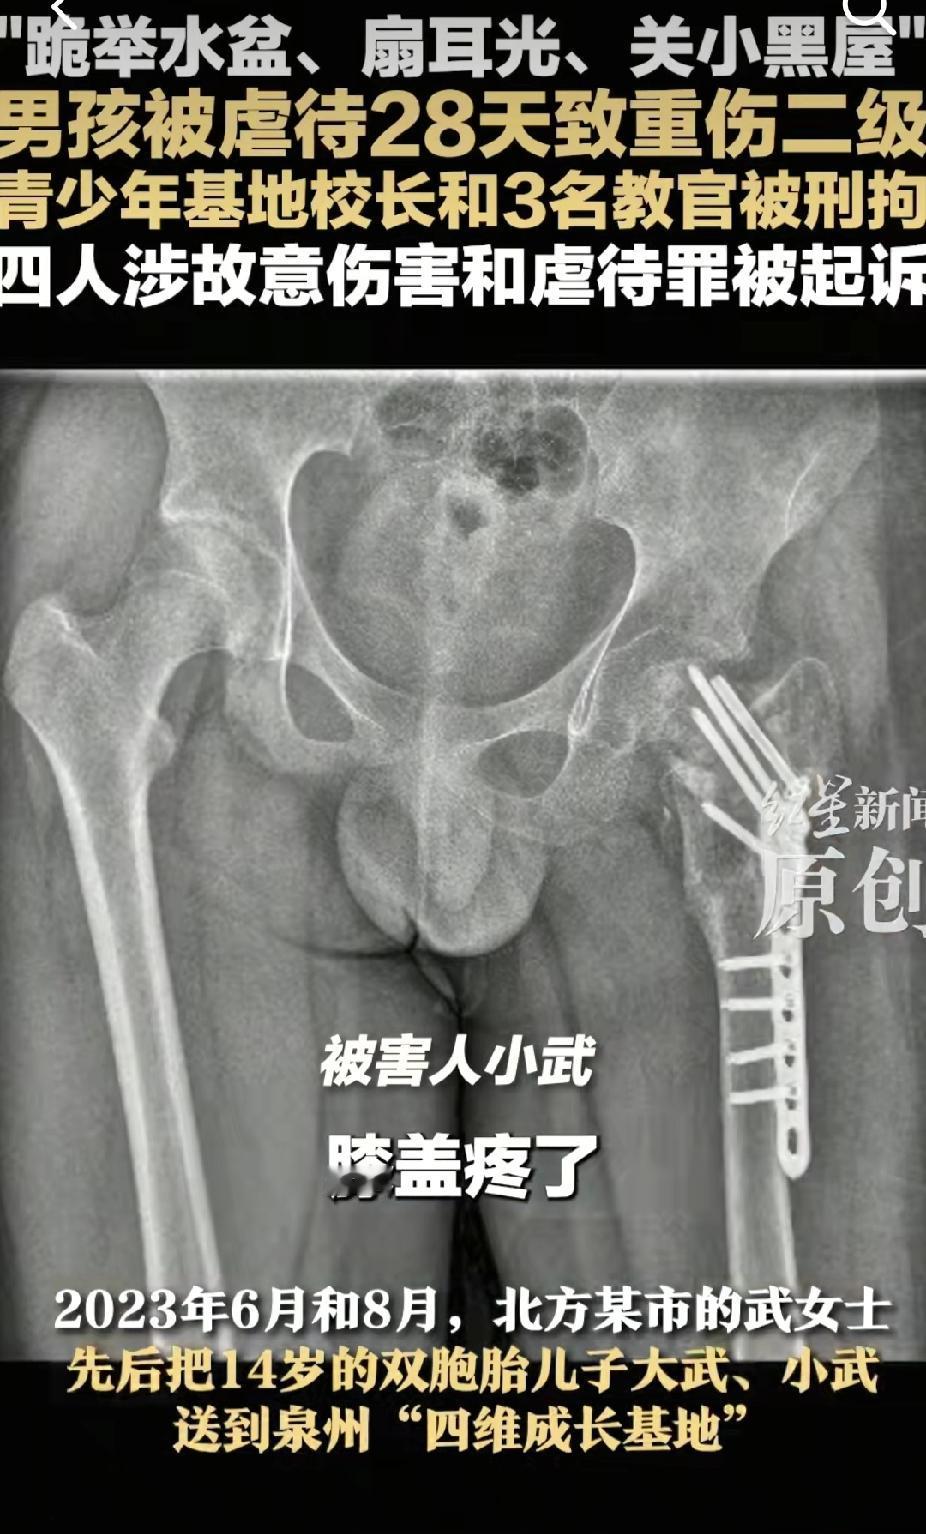

近日新闻泉州一青少年基地的校长和教官虐待一名男孩儿28天后,导致重伤二级。通过跪地举水盆儿、扇耳光、关小黑屋、殴打等多种虐待手段。男孩儿已经被折磨的遍体鳞伤,多处伤疤早已经感染,需拄拐杖行走,腿部有严重的伤口,骨骼也受到损伤,从X光片都可以清晰的看见。

男孩说他被打的膝盖疼了,躺在地上起不来,然而教官却认为他是装的。竟然再次将他摔倒,他的腿骨就好像被拉脱错位了,疼的起不来。然后校长走过来,在他受伤的腿脚又猛踹了一脚。简直都是畜生,没人性。